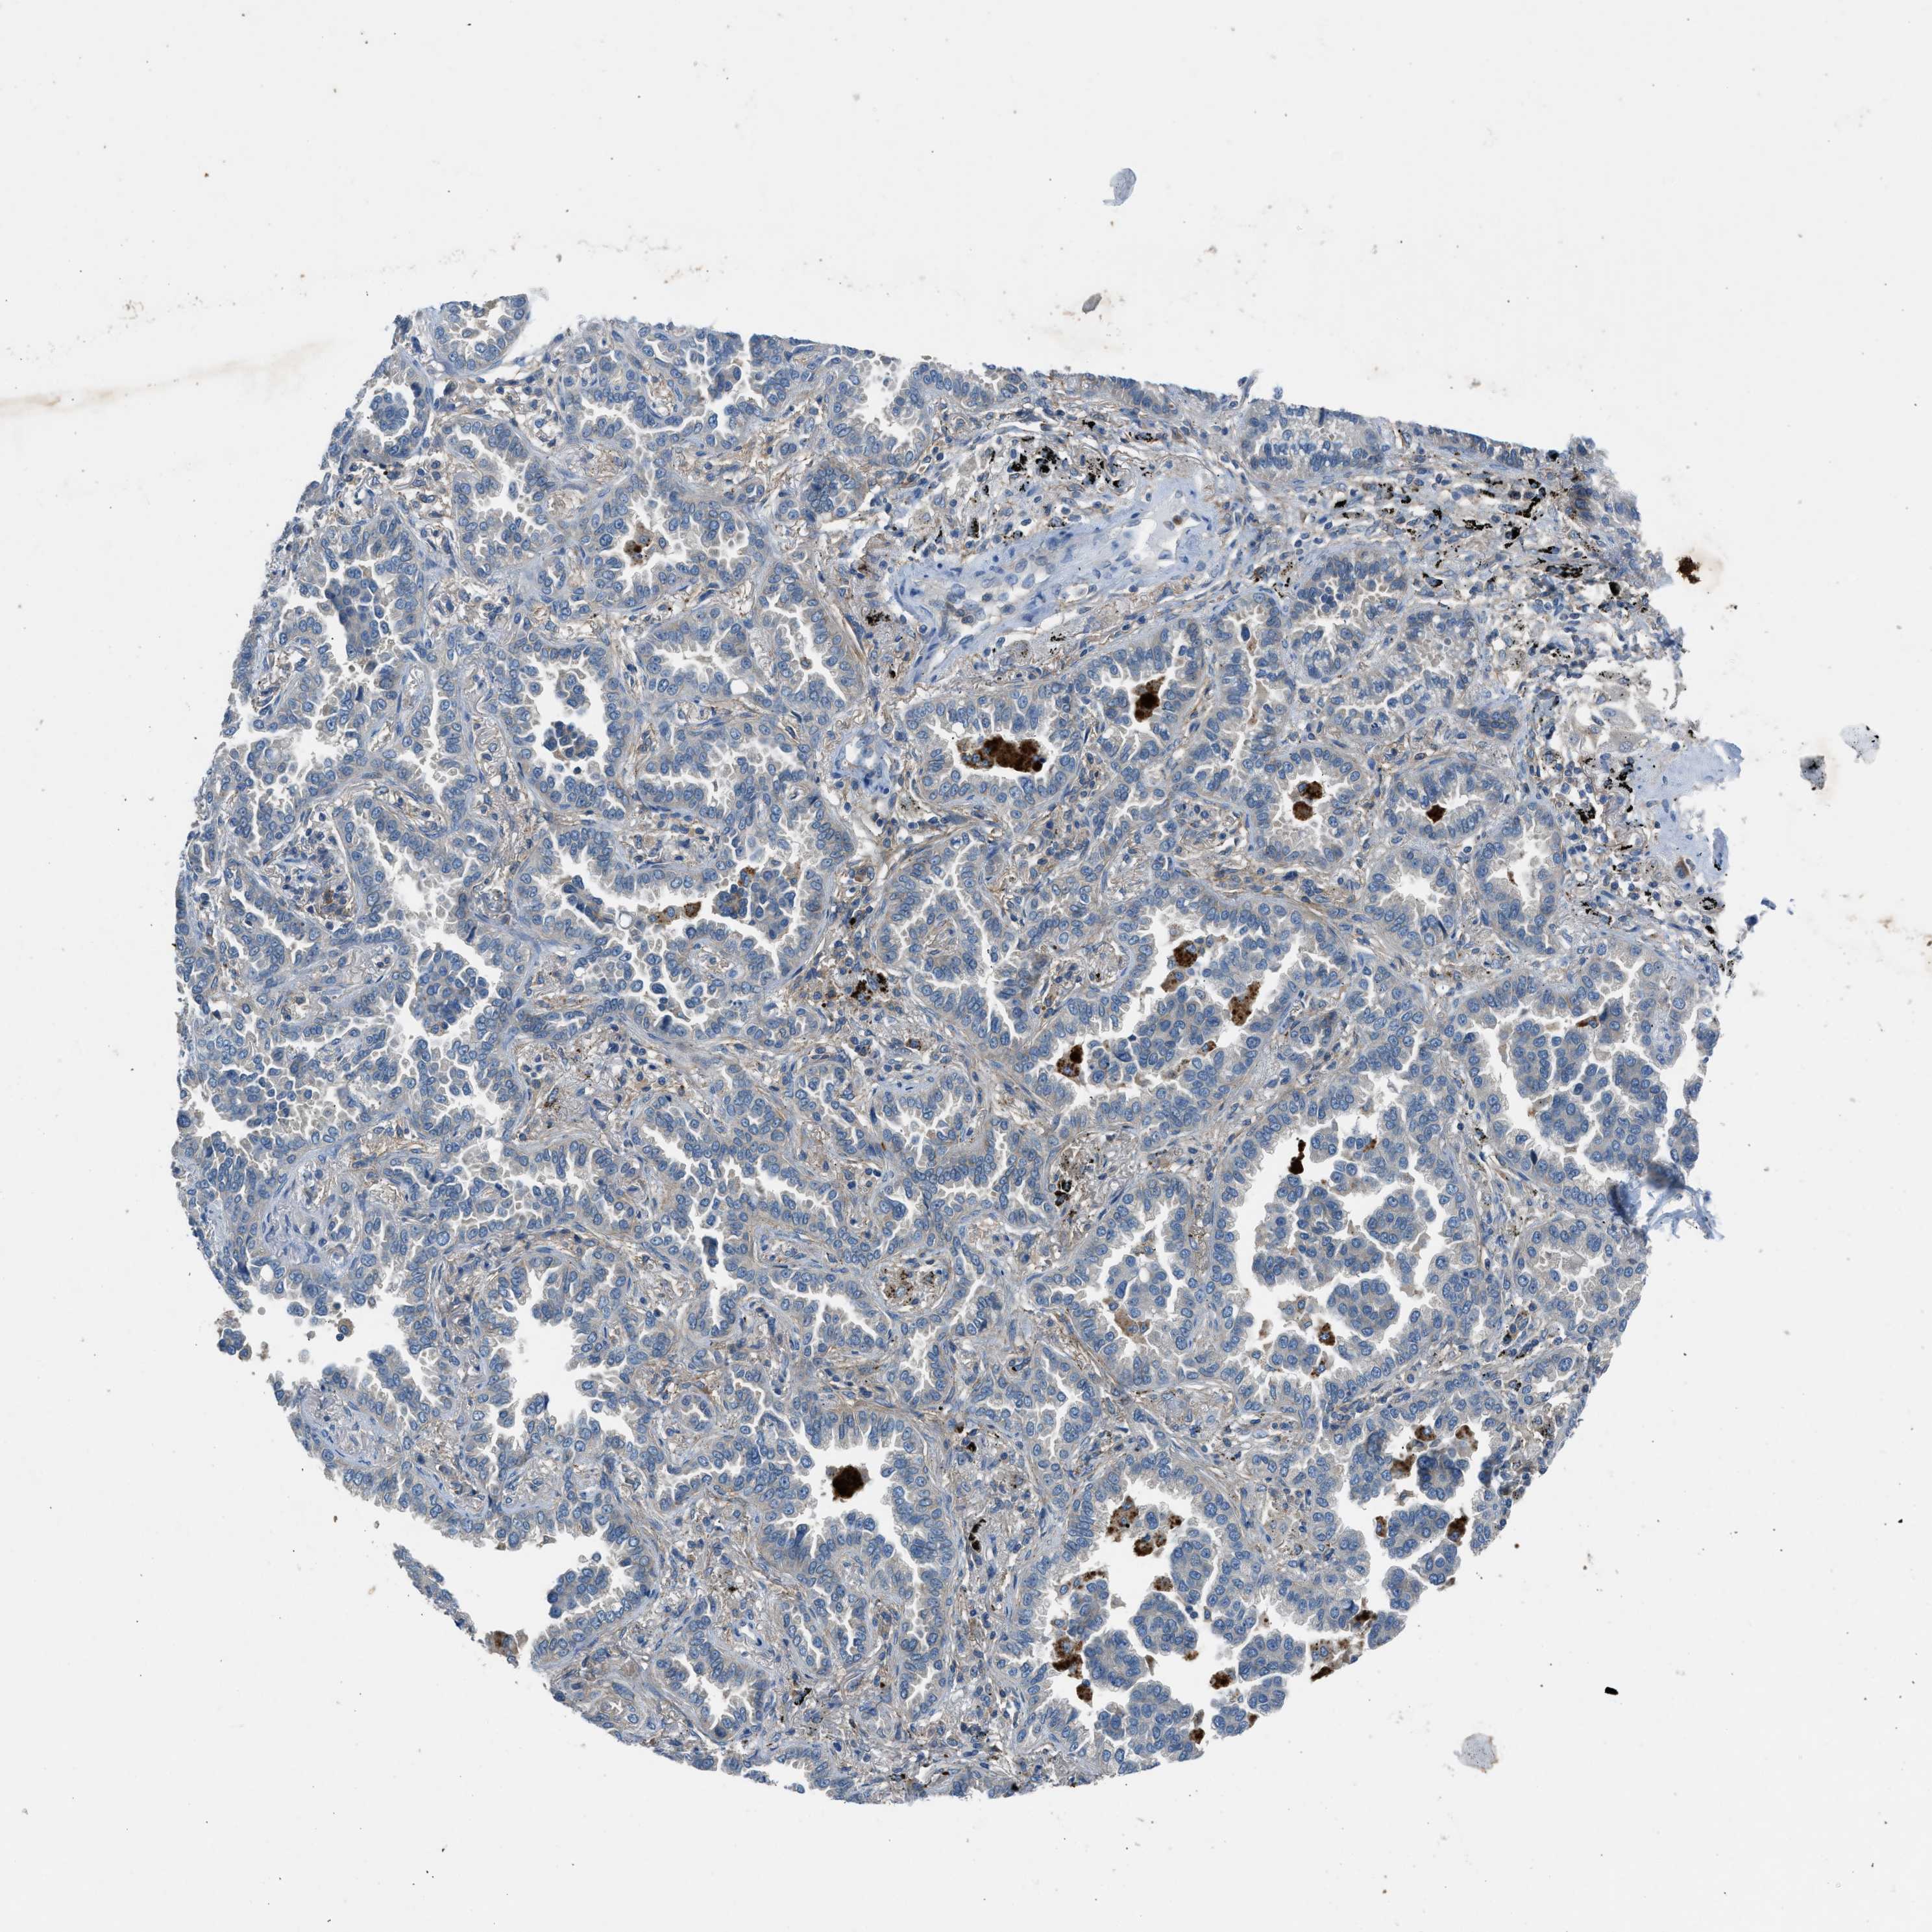

BMP1 is validated prognostic, high expression is unfavorable in Lung Adenocarcinoma (TCGA)

Best expression cut offi

: 11.37

Average pTPM 11.8

Number of samples 497